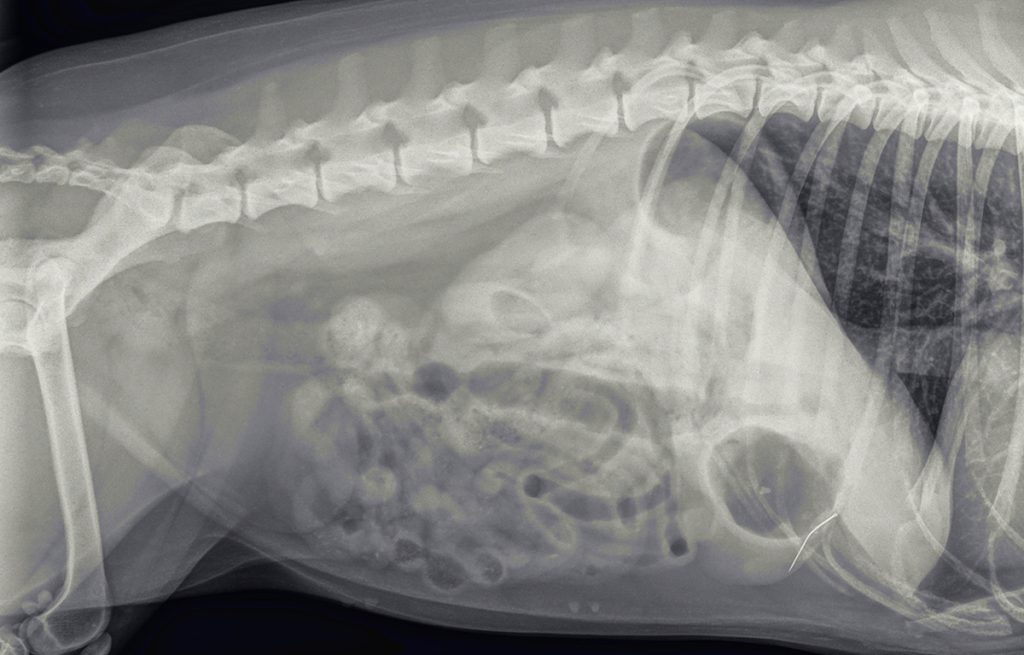

Ter controle, of de structuur nog in de buik aanwezig is, worden opnieuw röntgenfoto’s gemaakt. Hierop is het voorwerp nog goed zichtbaar, met een soort oogje erin. Het moet dus een naald zijn. De foto’s suggereren verder dat de naald niet in het maag-darmstelsel zit, maar in de buikholte.

Een paar dagen later is het zo ver. We maken voor de zekerheid opnieuw foto’s, om de juiste lokatie te controleren. De naald lijkt aardig op dezelfde plek te liggen.

Na het openen van de buik en het verwijderen van wat vet, is de chirurg gaan zoeken. Al snel vindt hij aan de voorzijde van de maag een vreemd vliesje. Dit blijkt een stukje vet en vlies te zijn, wat op het oogje van de naald verkleefd zat. Ruim 2/3 van de naald blijkt in een leverlob te zitten. De naald blijkt er niet eenvoudig uitgetrokken te kunnen worden. Hij zit aardig vast. Dit suggereert dat hij er misschien al iets langer zit. Bij het verwijderen van de naald ontstaat er een klein scheurtje in de lever. De bloeding kan worden gestelpt met een speciaal matje dat stolling bevordert. Hierna is het een kwestie van de buik sluiten en Lady mag weer wakker worden.

We zullen nooit helemaal zeker weten hoe de naald in de buikholte terecht is gekomen. Gezien de localisatie, de richting, het zwart zijn en het ontbreken van uitgebreide ontsteking er omheen is de gedachte dat hij in de maag gezeten heeft. Hier is hij door het maagzuur zwart geworden en steriel geworden. Waarschijnlijk is hij daarna door een maagbeweging door de wand heen gestoken. Lady heeft wat dat betreft veel geluk gehad; zou de naald de galblaas geraakt hebben of een groot bloedvat, dan was het anders afgelopen.